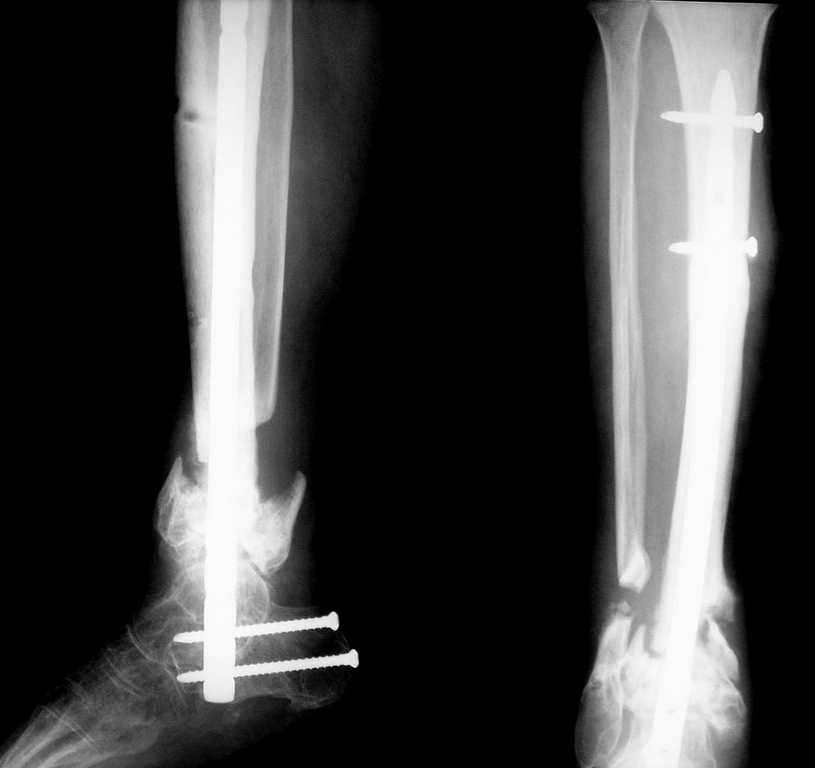

Re: Ложный сустав н/3 голени

Вот что в итоге получилось. Вопрос по поводу нагрузки: может сразу дать? и зря я поставил статический винт?